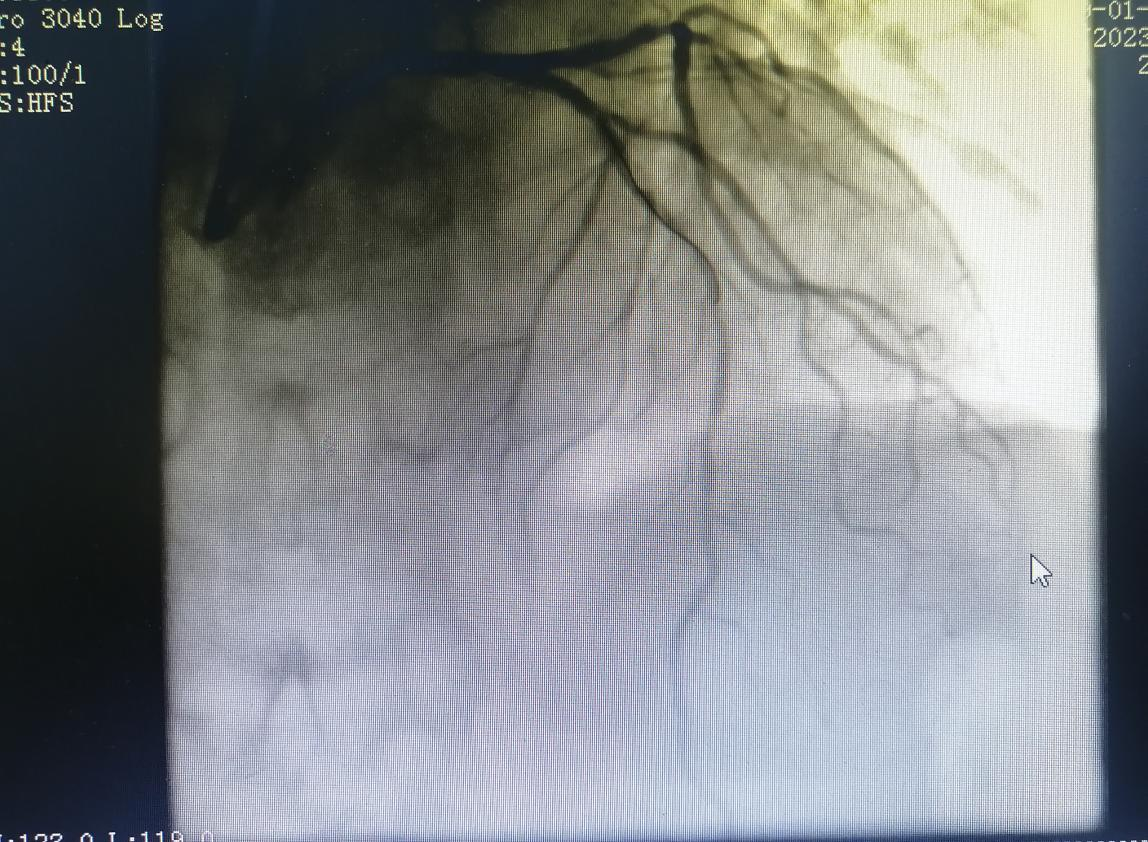

術(shù)前:

64歲的張阿姨,因“間斷胸悶3月余,加重5天余”入住心血管內(nèi)科。入院后,經(jīng)檢查冠脈造影提示冠脈前降支嚴(yán)重狹窄伴鈣化。

經(jīng)過(guò)充分的評(píng)估和準(zhǔn)備,在金叔宣教授的指導(dǎo)下,心血管科內(nèi)科介入團(tuán)隊(duì)為張阿姨制定了個(gè)體化的手術(shù)治療方案,即行血管內(nèi)超聲+冠狀動(dòng)脈旋磨術(shù)+冠脈支架置入術(shù)。